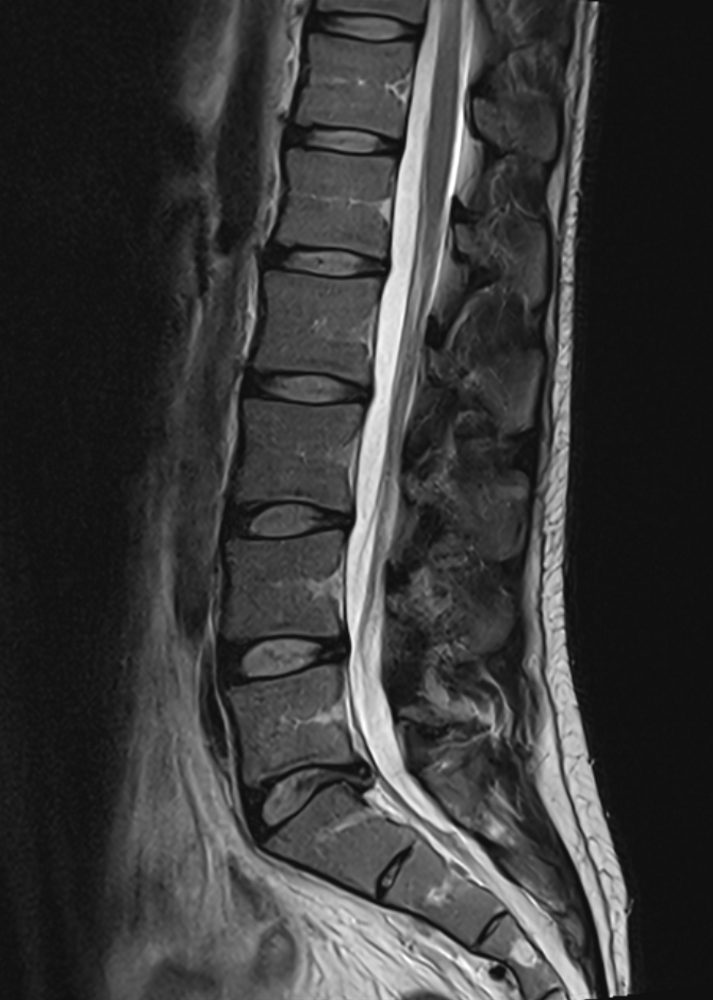

MRT der Wirbelsäule

Zur Untersuchung von Rückenproblemen, insbesondere im Fall von Bandscheibenvorfällen und Verschleißerkrankungen hat sich die Magnetresonanztomographie als äußerst nützliches diagnostisches Verfahren etabliert. Die MRT ermöglicht eine präzise Darstellung der Wirbelsäule einschließlich der Bandscheiben, Wirbelkörper und Nervenwurzeln. Dadurch können etwa Bandscheibenvorfälle erkannt werden. Bei einem Bandscheibenvorfall verändert die weiche Bandscheibe zwischen den Wirbeln ihre Position und verursacht, indem sie auf Nerven drückt, Schmerzen und Beschwerden. Auch Verschleißerkrankungen wie Arthrose der Wirbelsäule oder entzündliche Erkrankungen (sogenannte Spondylarthritis) können durch die MRT diagnostiziert werden. Ihr behandelnder Arzt kann dadurch den Grad der Degeneration und damit auch die entsprechenden möglichen Behandlungsansätze beurteilen.